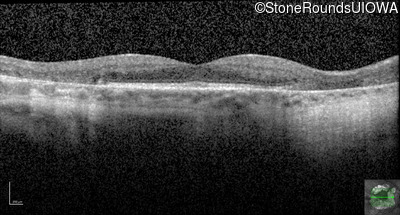

Age at visit: 59 years

This 59 year old woman first experienced defects in her mid peripheral field in the past year. Her hearing worsened in her 30's and she started wearing hearing aids at age 40. She was diagnosed with diabetes at age 39 and began using insulin at age 42.